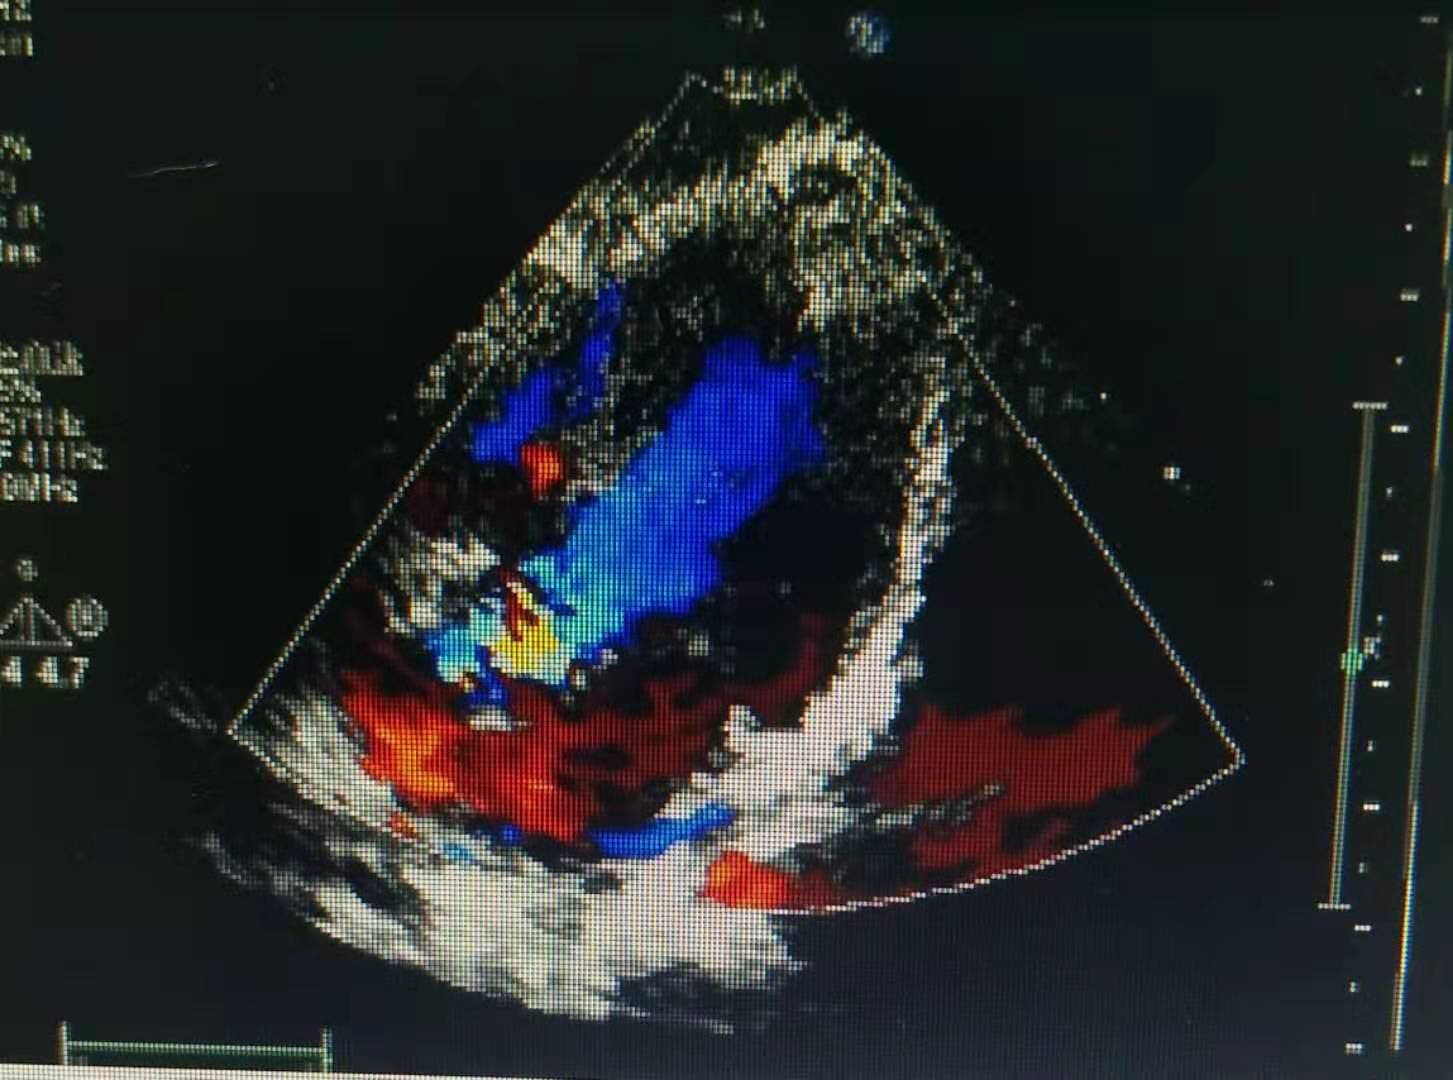

入院后赶紧完善各项相关检查,查新冠病毒核酸测定正常;流感A+B病毒抗原检测:阴性;血常规五分类:白细胞数目(WBC),17.66x10^9/L,H;中性粒细胞百分比(NEUT%),83.4%,H;淋巴细胞百分比11.6%,L;血红蛋白浓度(HGB),104g/L;血小板数目323x10^9/L,H;中性粒细胞绝对值14.72x10^9/L;外周血涂片异淋细胞2%;粪便常规+隐血试验:正常;血清C-反应蛋白(CRP),106.49mg/L,H;电解质六项、血清肌钙蛋白Ⅰ测定、轮状病毒未见异常;葡萄糖6-磷酸脱氢酶活性检测(G6PD),2662U/L ;降钙素原(PCT),0.959ng/ml,H。心脏彩超未见异常。EB病毒阴性。

第三天查房时患儿还是间中发热,但是低热为主,间隔时间明显延长,间中咳嗽、痰鸣、鼻塞,无抽搐,无明显气喘,解烂便,无伴黏液、脓血,精神、睡眠、饮食一般,小便可 。患儿病情好转,继续予抗感染、静注人免疫球蛋白治疗,予思连康调节肠道菌群失调,予阿司匹林抗血小板治疗,同时注意是否有指端、肛周脱皮,必要时复查心脏彩超了解冠状动脉是否扩张。